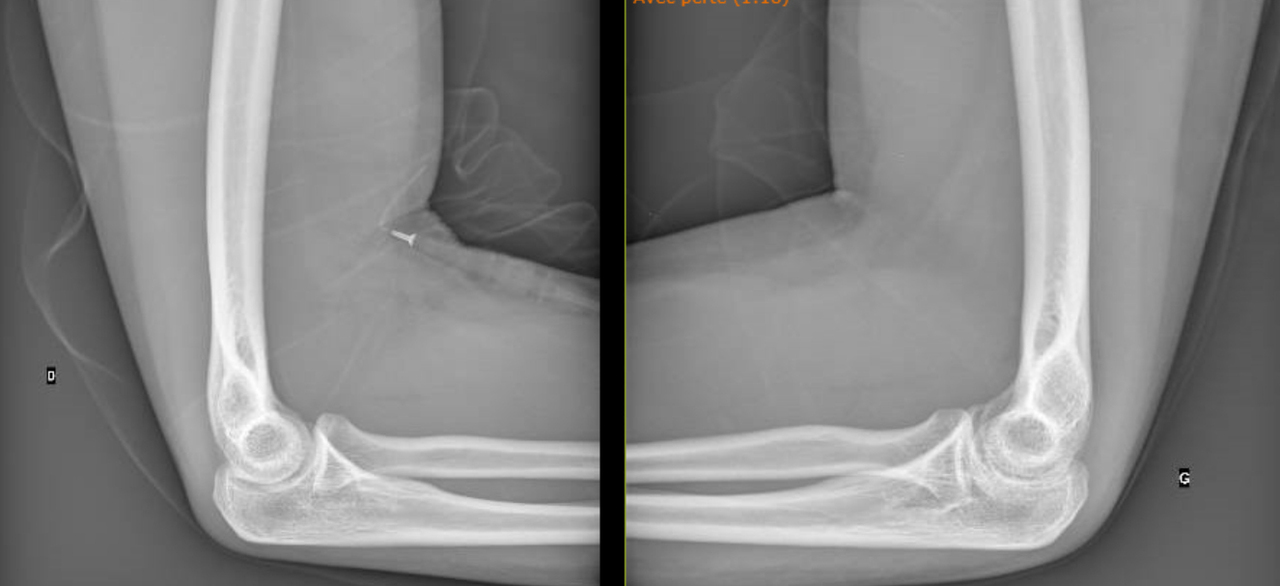

Vous la revoyez quatre mois après la fin de l’antibiothérapie avec des radiographies de contrôle (fig. 3 et 4).

Figure 3 (Source Salomé Abdellaoui, La Revue du Praticien)

Figure 4 (Source Salomé Abdellaoui, La Revue du Praticien)

On voit sur les radiographies que l’articulation est abîmée avec un pincement articulaire à gauche, il y a donc peu de chance que le flessum récupère totalement.

Il n’y pas de douleur ou de retentissement fonctionnel associé au flessum de coude donc pas d’indication actuelle à une prise en charge chirurgicale. En revanche, l’articulation va probablement évoluer vers une arthrose précoce et possiblement vers la mise en place d’une prothèse dans un second temps.